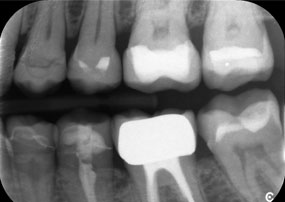

El reto consistía en extraer doce coronas bloqueadas con aleación común sin dañar los raigones subyacentes. Se utilizó el contra-ángulo para realizar incisiones precisas en las capas de cerámica y separar las estructuras metálicas con una fresa de metal duro, con el fin de extraer las coronas con un traumatismo mínimo. En solo 30 minutos se retiraron las coronas antiguas y se pudo preparar el nuevo trabajo, compuesto por zirconio completo en la zona posterior y coronas con recubrimiento en la zona anterior. El resultado fue una reconstrucción completa, satisfactoria tanto desde el punto de vista funcional como estético (véase la fig. 1).

Una radiografía de la mandíbula de un paciente de 81 años, sobre un fondo negro.

Figura 1: Rehabilitación estética de coronas de metal-cerámica: extracción completa y sustitución de coronas de metal-cerámica de 40 años de antigüedad para mejorar la estética en una paciente de 81 años.